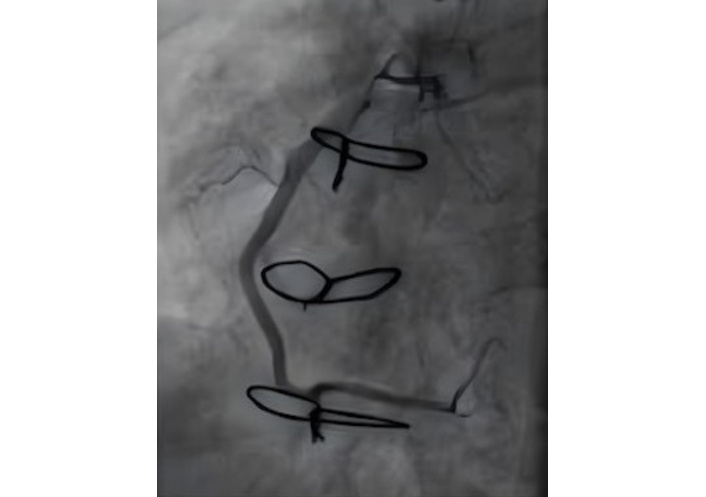

A TTE evaluation performed three months later did not report the mass seen on CXR as a possible pseudoaneurysm (Figure 4). The mass on the left side became more prominent on CXR (Figure 5), nineteen months later. A thoracic CT scan revealed a giant pseudoaneurysm on the posterior wall of LV which was 10 cm × 7 cm in size (Figure 6). The patient was urgently transferred to our center for definitive management, where a coronary angiography (CA) was performed. CA showed normal coronary anatomy (Figures 7 and 8), but left ventriculography confirmed the diagnosis: leakage of contrast medium into the pseudoaneurysm sac was clearly observed (Figures 9 and 10).

Ventricular angiography has been traditionally considered the “gold standard” for the diagnosis of pseudoaneurysms. Currently, this diagnostic technique is only applied in a limited number of cases due to its time-consuming nature and the risk of pseudoaneurysm rupture [8]. In this case, besides showing normal coronary anatomy, it also allowed us to clearly measure the pseudoaneurysm size and provided information about the complete filling of the sac and the absence of thrombi. Cardiac CT or magnetic resonance image (MRI) is also the most definitive test, and the information they provide is essential for early diagnosis and appropriate treatment planning [9, 10].